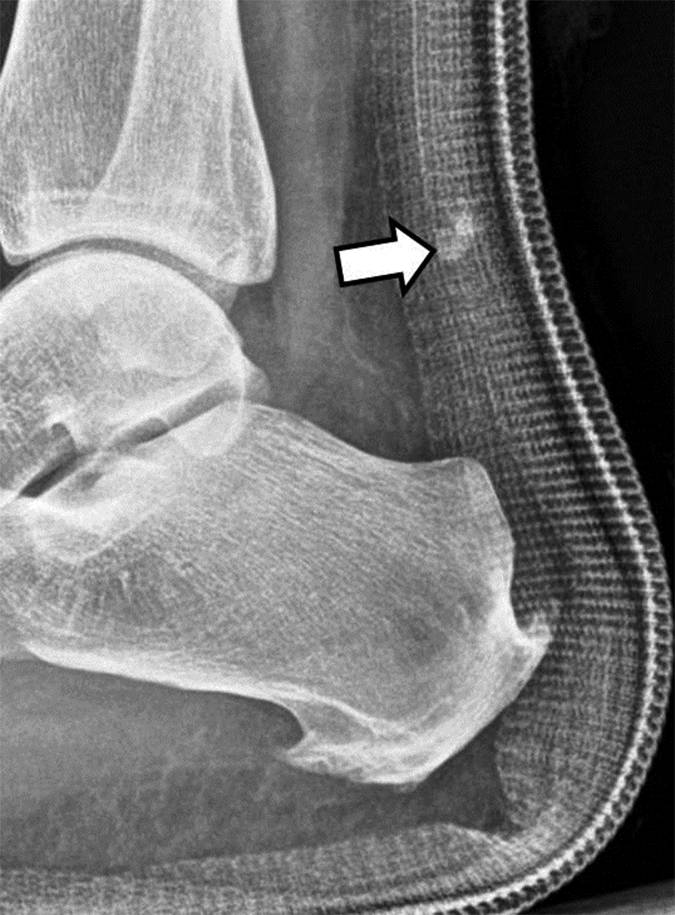

图 5B - 27岁的男性棒球运动员在运动加速后急性足跟疼痛。 侧位X线照片显示内侧足底过程中的线性断裂(箭头)。